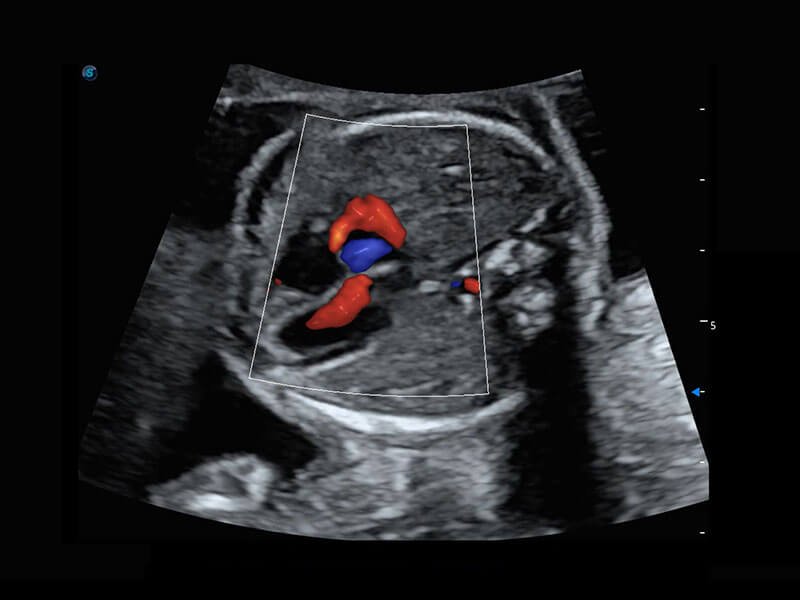

乳腺超声 / 新生儿

P60搭载宽频带线阵探头、宽景成像、弹性成像技术,为您提供乳腺应用方案。P60支持高频相控阵探头、线阵探头、腹部高频探头、腹部微凸探头等,丰富的探头群搭载敏感的彩色血流成像,适用于新生儿多种脏器检测要求,满足新生儿筛查需求。

• 新生儿心脏